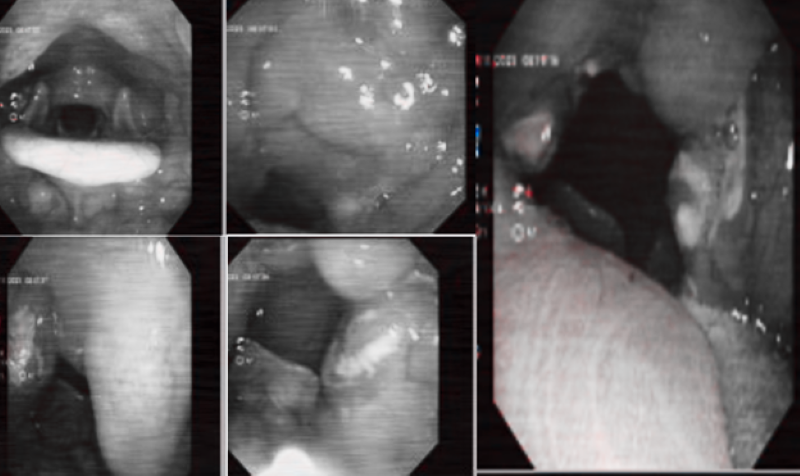

Kết quả nội soi tai mũi họng phát hiện niêm mạc họng nề đỏ, amidan hai bên quá phát có nhiều giả mạc mủ. Chẩn đoán xác định, bệnh nhân mắc Viêm amidan cấp mủ. Bác sĩ chỉ định phác đồ điều trị bằng kháng sinh, giảm viêm, giảm đau tại chỗ.

Kết quả nội soi tai mũi họng của bệnh nhân